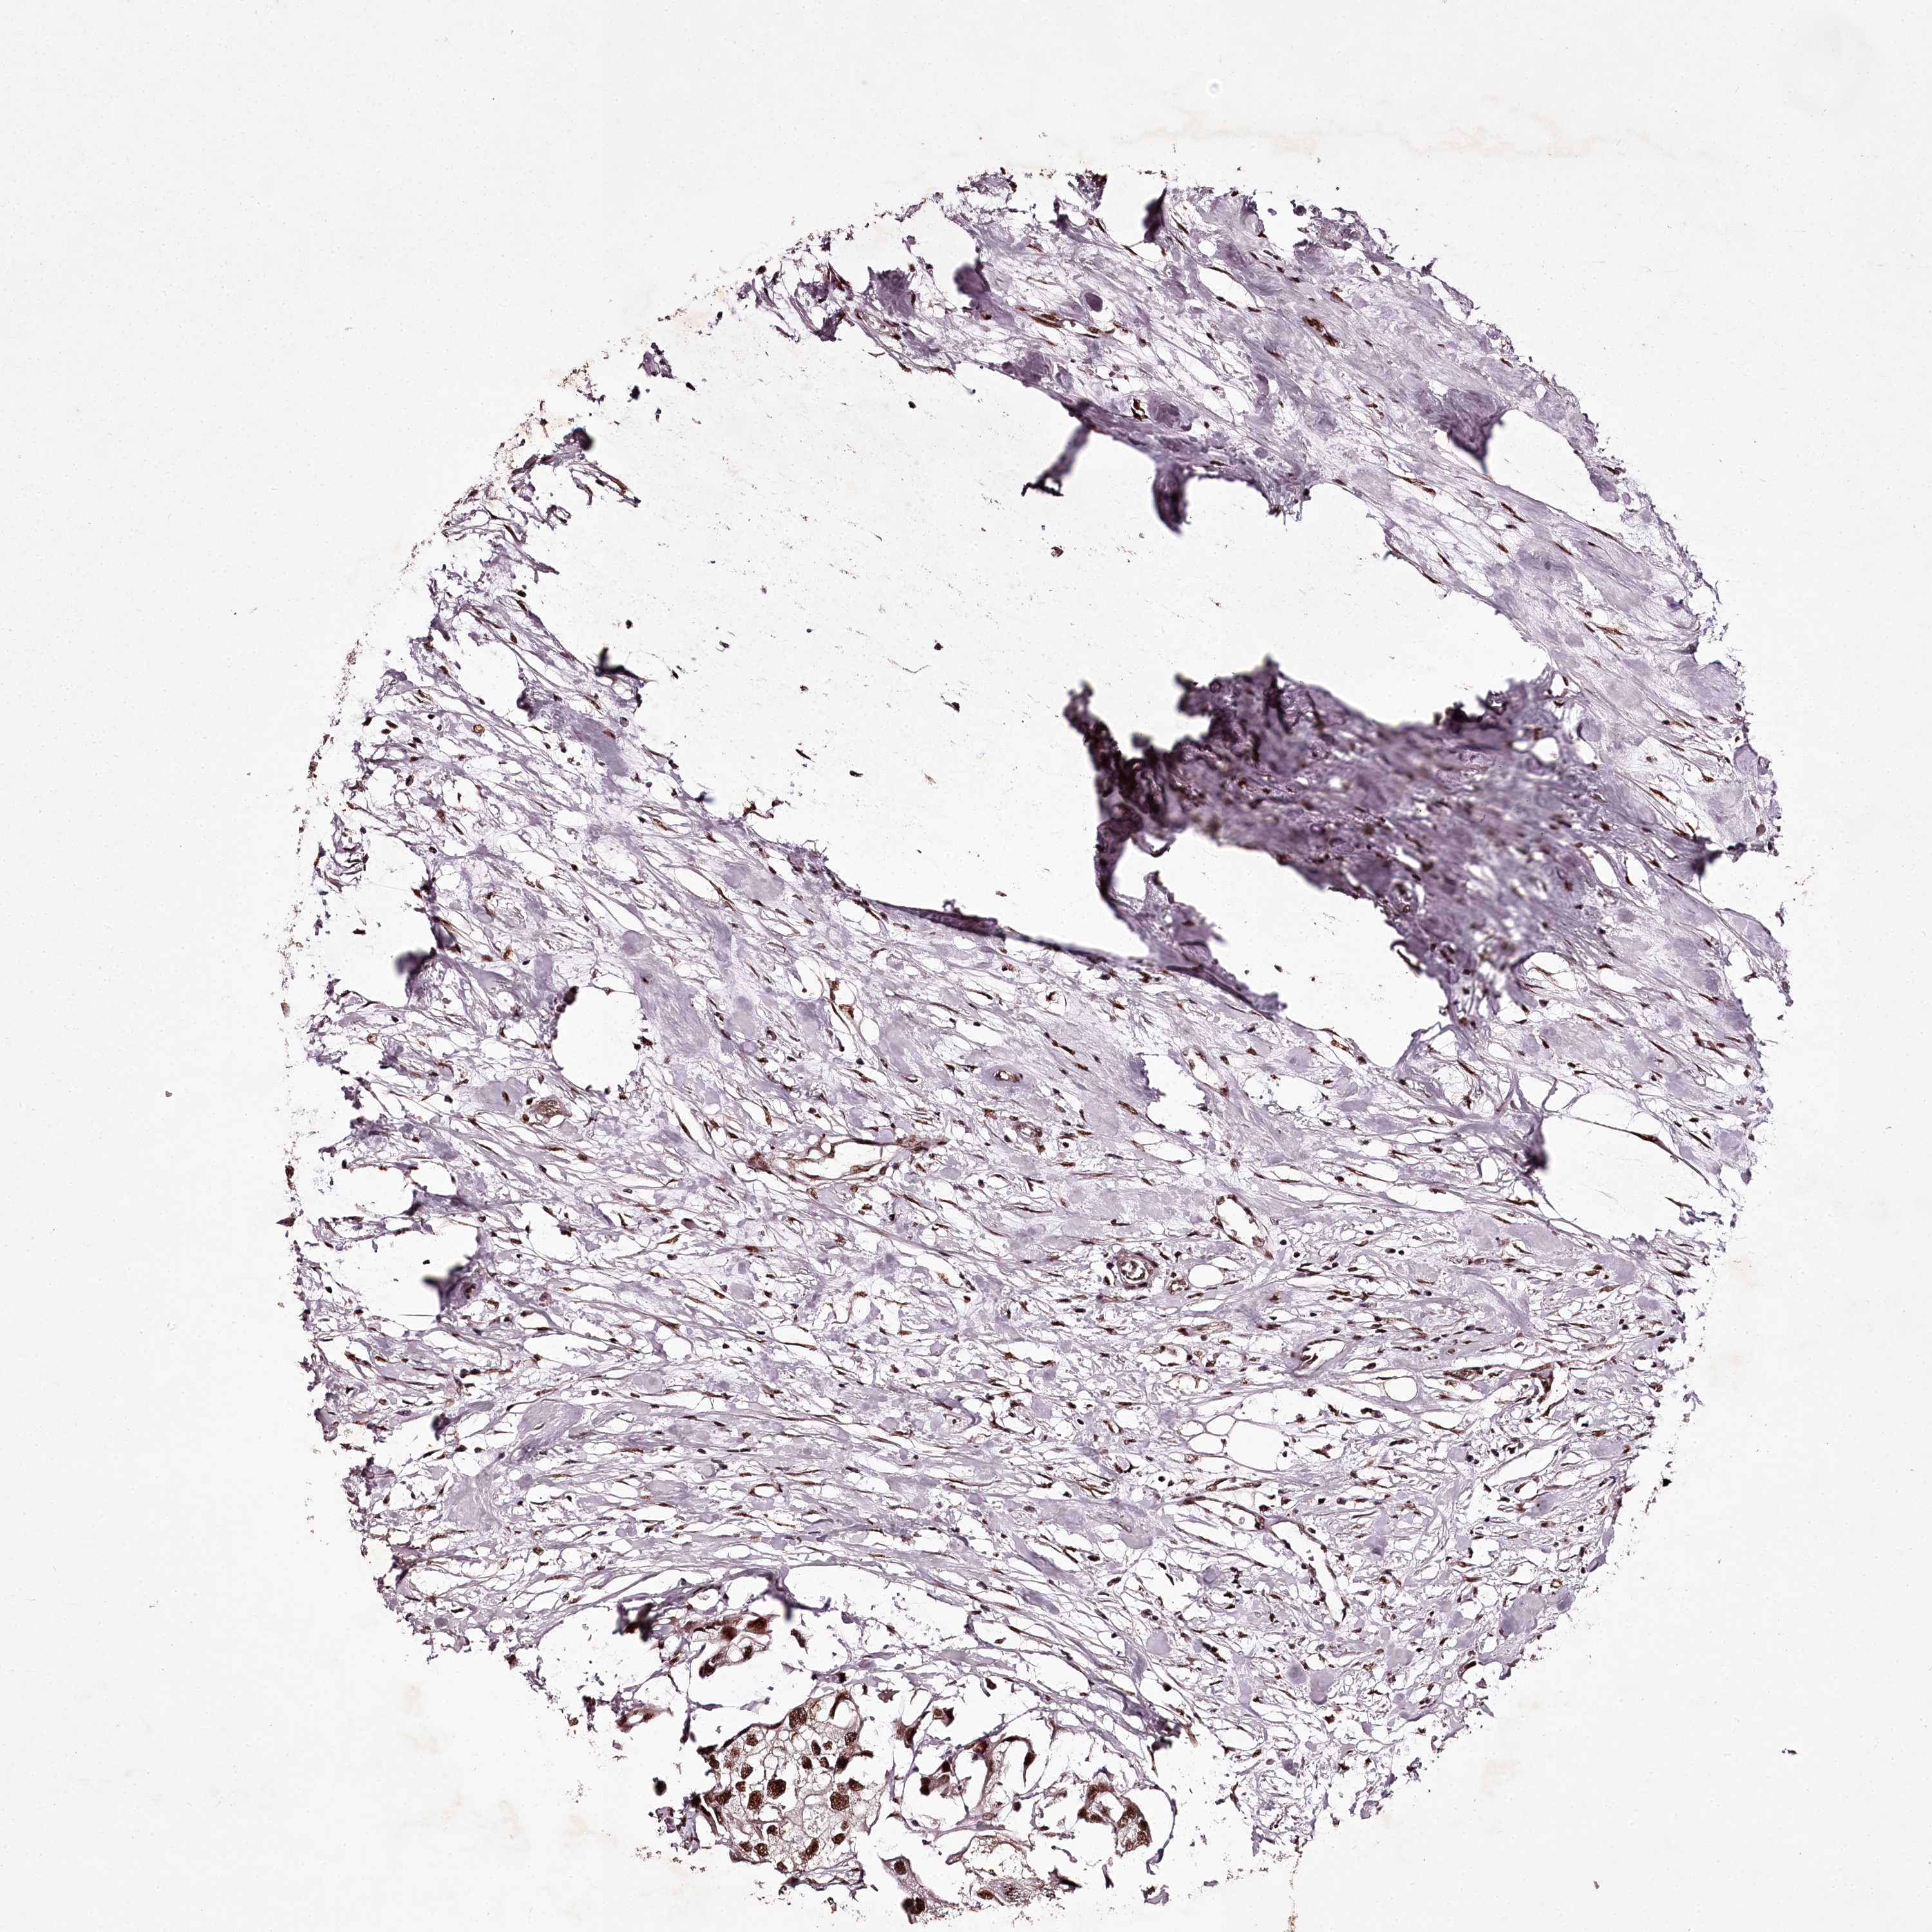

UROTHELIAL CANCER - Protein expressioni

A mouse-over function shows sample information and annotation data. Click on an image to view it in a full screen mode. Samples can be filtered based on level of antibody staining by selecting one or several of the following categories: high, medium, low and not detected. The assay and annotation is described here.

Note that samples used for immunohistochemistry by the Human Protein Atlas do not correspond to samples in the TCGA dataset.

Antibody stainingi

Antibody staining in the annotated cell types in the current human tissue is reported as not detected, low, medium, or high, based on conventional immunohistochemistry profiling in selected tissues. This score is based on the combination of the staining intensity and fraction of stained cells.

Each image is clickable and will lead to virtual microscopy that enables deeper exploration of all samples and also displays staining intensity scores, fraction scores and subcellular localization as well as patient and tissue information for each sample.

Antibody HPA038904

Staining

High

Medium

Low

Not detected

Intensity

Strong

Moderate

Weak

Negative

Quantity

>75%

75%-25%

<25%

None

Location

Nuclear

Cytoplasmic/membranous

Cytoplasmic/membranous,nuclear

Urothelial carcinoma, High grade

Urothelial carcinoma, Low grade